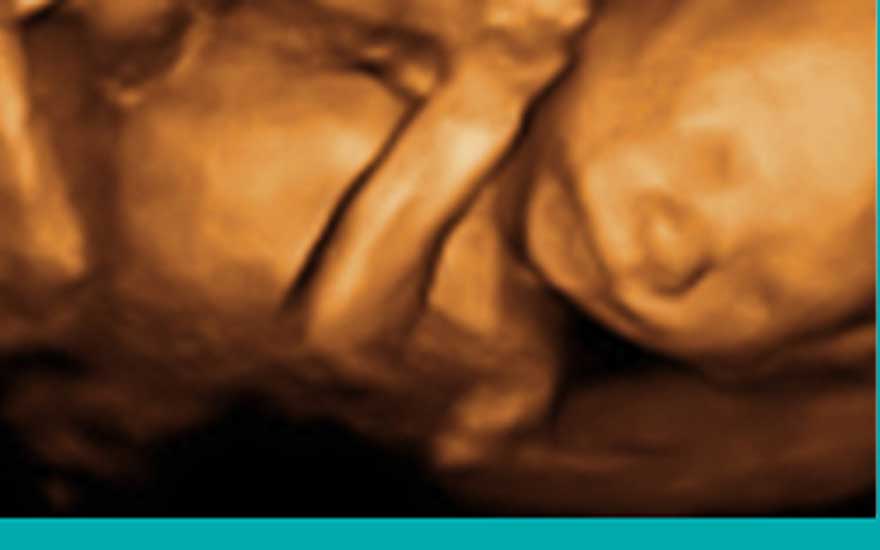

El bebé mide unos 20 centímetros y pesa casi un cuarto de kilo. Ya están formados los órganos vitales, es por ese motivo por el que se va a realizar la ecografía más completa del embarazo. Se tratará de descartar cualquier tipo de malformación. Sus órganos internos están ya en una fase de desarrollo muy avanzada, el bebé no está aún preparado para vivir fuera del útero materno de forma independiente. En condiciones normales, a las 20 semanas de gestación ya han aparecido todos los movimientos fetales (movimientos de tronco, extremidades, movimientos respiratorios…) alcanzando su máximo nivel de movimiento hasta la semana 28.